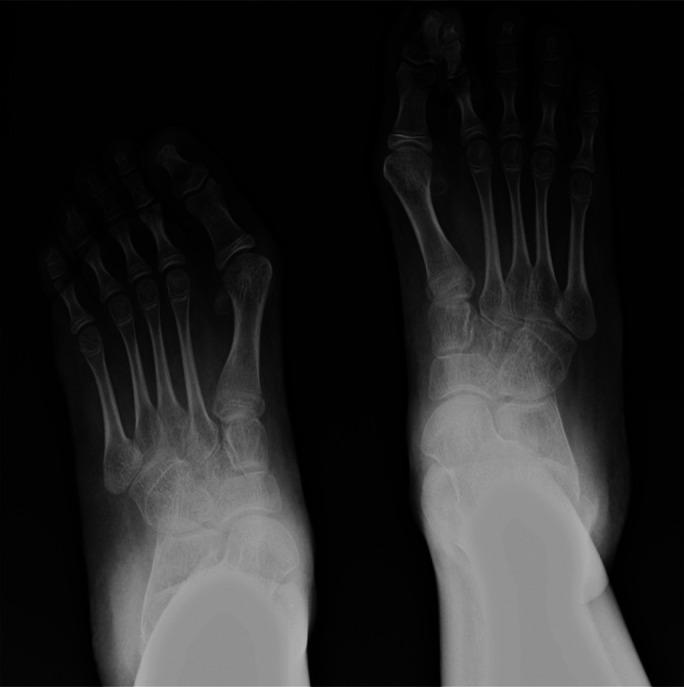

A dorsal bunion may occur in nonambulatory adolescents with cerebral palsy (CP) and a Gross Motor Function Classification System (GMFCS) level of IV or V. The deformity can cause pain, skin breakdown, and difficulty wearing shoes and braces. A consensus on the biomechanics and surgical management of dorsal bunions in persons with severe CP has not been established.

This retrospective cohort study included 23 nonambulatory adolescents with CP, GMFCS level IV or V, and symptomatic dorsal bunions requiring surgery. The median age at surgery was 17 years, and the median follow-up was 56 months. Reconstructive surgery included the excision of a 2 to 3-cm segment of the tibialis anterior tendon to correct the elevation of the first metatarsal. The fixed deformity of the first metatarsophalangeal joint was managed with use of corrective arthrodesis and dorsal plate fixation. Clinical and radiographic outcomes were assessed preoperatively and postoperatively at the transition to adult services.

There were significant improvements in the clinical and radiographic outcome measures (p < 0.001). Pain was relieved, and there were no further episodes of skin breakdown. The elevation of the first metatarsal was corrected from a mean of 3° of dorsiflexion to a mean of 19° of plantar flexion. The deformity of the first metatarsophalangeal joint was corrected from a mean of 55° of plantar flexion to a mean of 21° of dorsiflexion. Six patients had complications, all of which were grade I or II according to the modified Clavien-Dindo system.

The surgical reconstruction of a dorsal bunion via soft-tissue rebalancing of the first ray and corrective arthrodesis of the first metatarsophalangeal joint resulted in favorable medium-term clinical and radiographic outcomes in nonambulatory adolescents with CP.